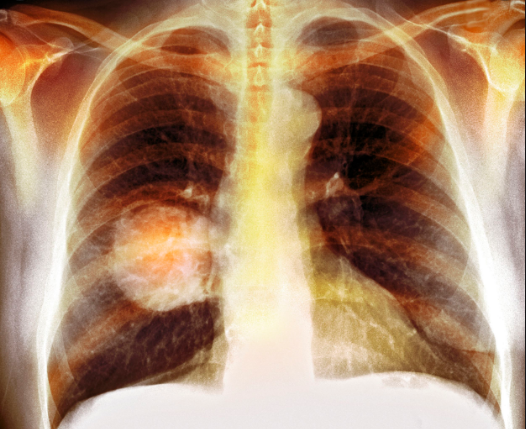

- Ung thư phổi: Đây là một trong những biến chứng nghiêm trọng nhất của bệnh viêm phế quản, ảnh hưởng trực tiếp đến tính mạng, cuộc sống của người bệnh.

Ung thư phổi là một trong những biến chứng nguy hiểm của viêm phế quản mạn